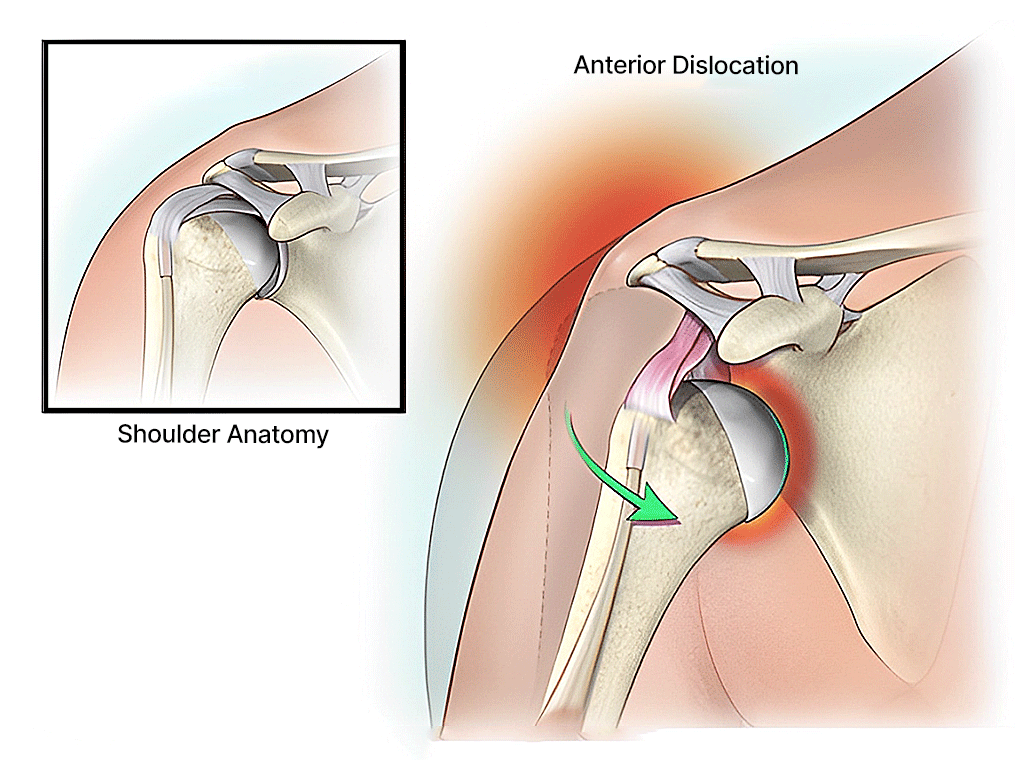

Dislocation